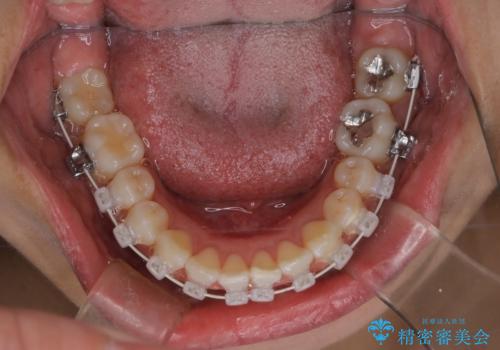

【審美装置】上下の前歯をきれいにしたい

- 矯正装置

- 審美装置

- 治療期間

- 1年8ヶ月

- 上下前歯のがたつきを主訴に来院されました。

口元も下げたいということもあり、上2本抜歯を行い治療を行いました。

抜歯を行い、前歯のがたつき、前歯の出ているところを改善できました。

患者様の満足感も高く治療を終えられました。